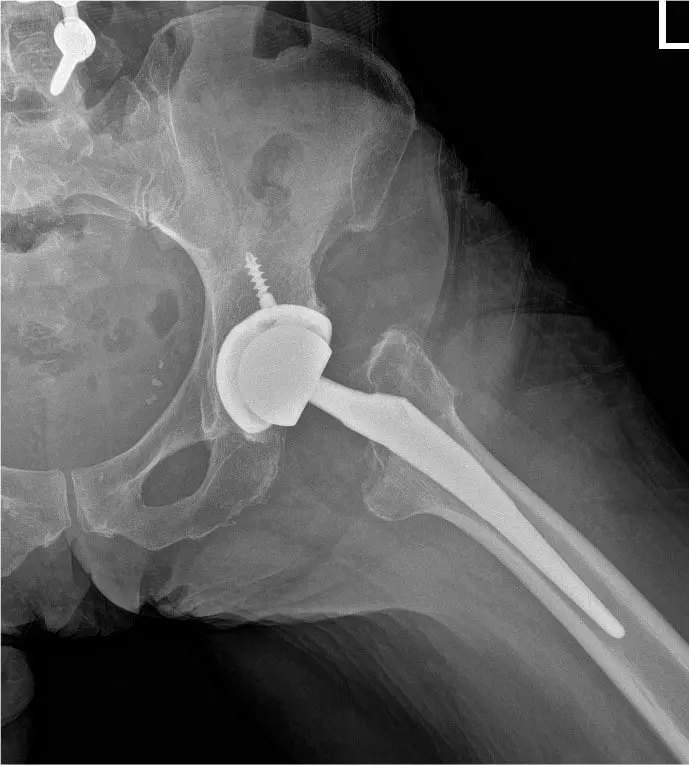

Bilateral Total Hip Replacement in a 65 yr old female

Post operative view xray of the hip